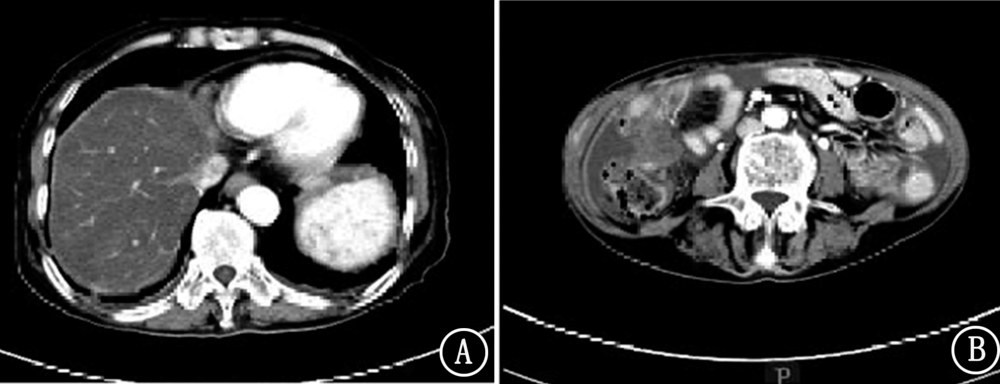

晚期胃癌目前无明确有效治疗手段,现报道1例安罗替尼治疗晚期胃癌病例,并对其临床疗效和安全性进行分析。